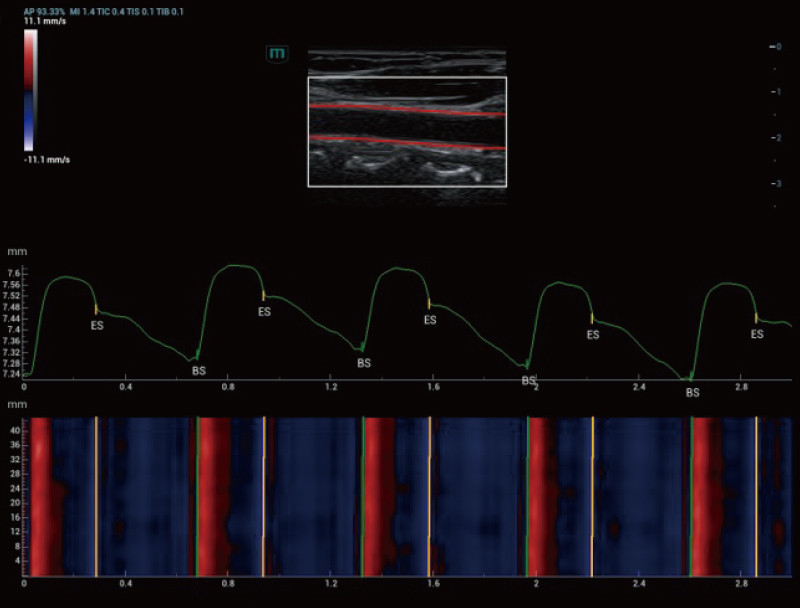

De Resona A20 introduceert een nieuwe generatie vasculaire, kwantitatieve analysetools met op RF-gegevens gebaseerde analyse van vasculaire pulsgolfsnelheid en wandschuifspanning. Deze ontwikkelingen helpen bij de beoordeling van arteri?le vasculaire sclerose.

Holo-PWV

Arteria carotis | Holo-PWV